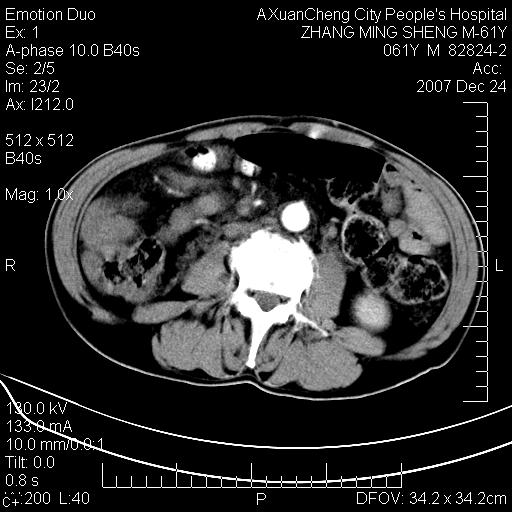

标题: CT11031:M61Y,胰腺占位 [打印本页]

标题: CT11031:M61Y,胰腺占位

大家侃侃门静脉和胆管系统怎么回事,肝内转移?

2,肝内多发结节状低密度占位,伴门脉及肠系膜上v栓子形成.考虑a;门脉及肠系膜上v血栓后肝改变.b;弥漫型肝癌伴门脉及肠系膜癌栓.

肝硬化,门脉高压,脾肿大;弥漫性肝癌,肝内、门脉、腹膜后淋巴结转移,肝内外胆管扩张,胰头区占位,建议mr检查

胰腺癌伴肝内转移;门脉、肠系膜上v癌栓形成。

考虑为:胰腺癌伴肝脏转移、腹膜后淋巴结转移,门静脉及肠系膜上静脉瘤栓形成。

胰体尾癌伴肝内转移,门静脉及肠系膜上静脉瘤栓形成.